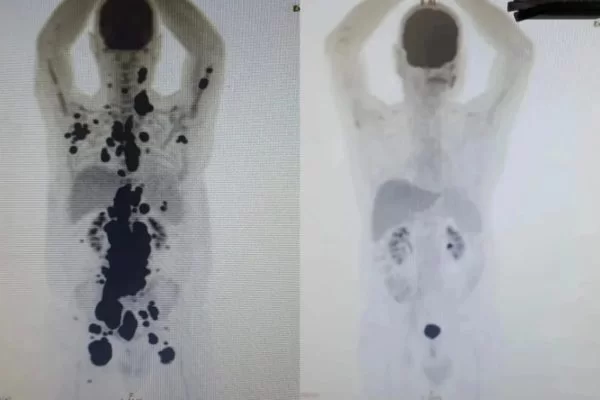

Uma terapia contra o câncer que está sendo testada no Brasil permitiu que um paciente diagnosticado há 13 anos tivesse a remissão completa de tumores em apenas um mês. Ele é um dos 14 pacientes atendidos na rede pública de saúde que estão sendo acompanhados em estudos com a terapia celular CAR-T.

O paciente Paulo Peregrino, 61 anos, vivia com um linfoma há cinco anos e já tinha tido outros tumores nos últimos 13 anos. O estágio da doença já era tão avançado que ele estava prestes a ser levado aos cuidados paliativos quando foi selecionado para testar a nova técnica.